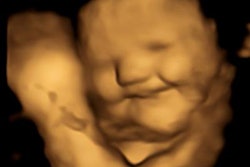

Contrast-enhanced ultrasound demonstrates testicular infarction in a case of spermatic cord torsion. Image courtesy of Prof. Paul Sidhu.In some countries, such as China and Russia, the trend was for ultrasound practitioners "only to do ultrasound, nothing else."